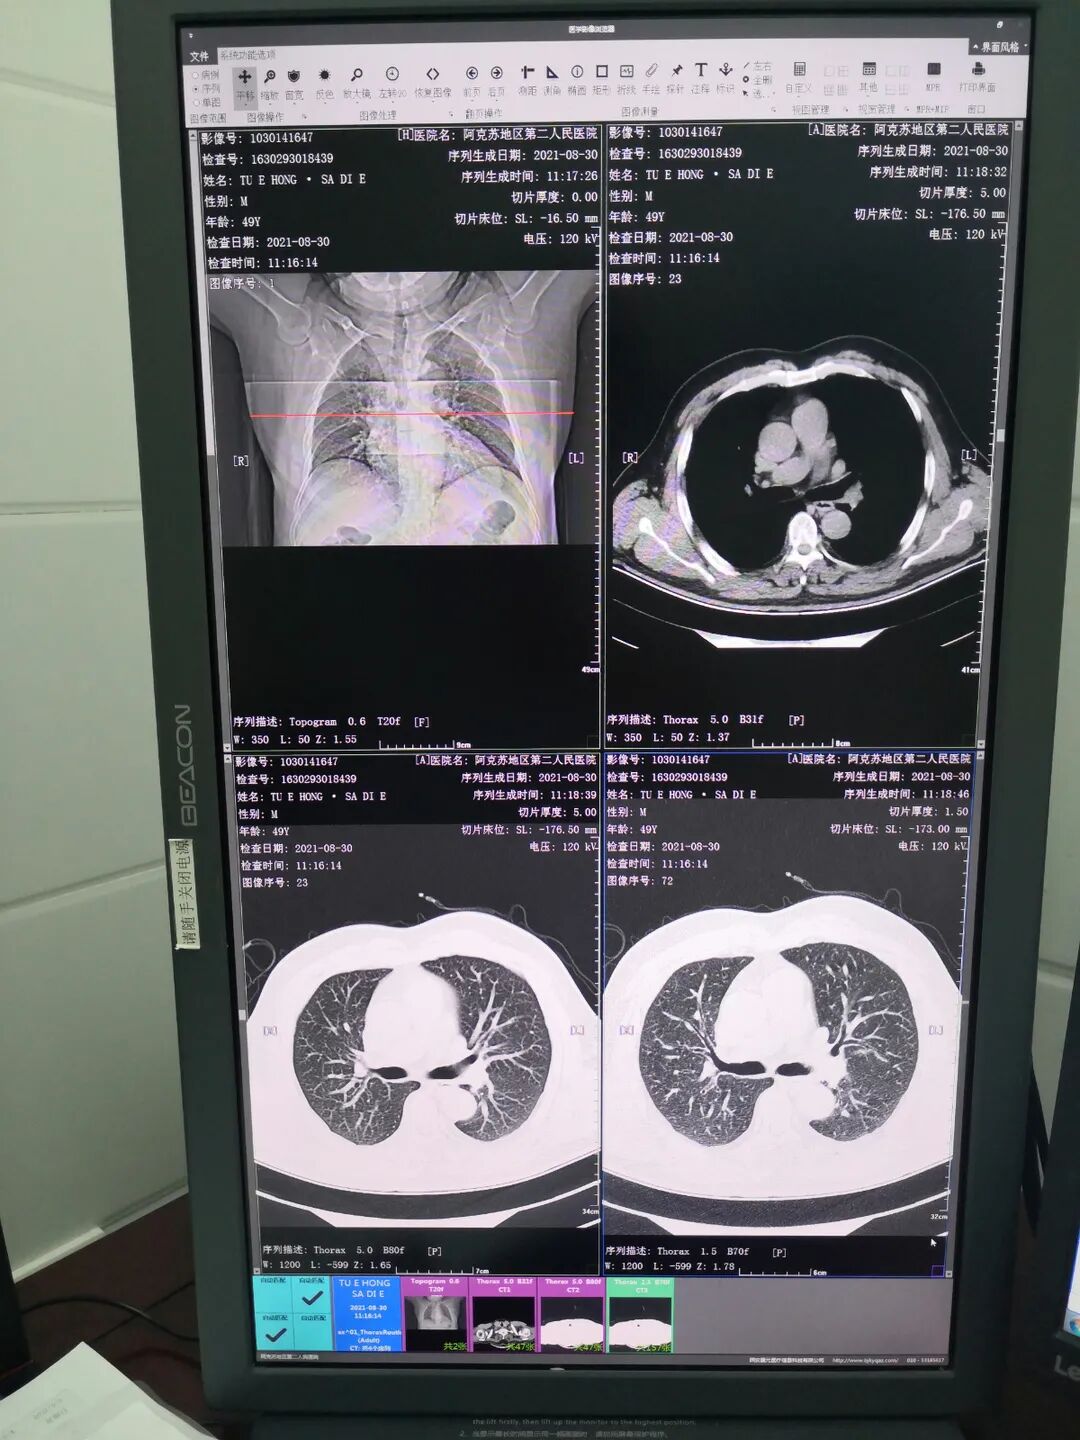

肺部CT图像                                 脑部磁共振图像

CT检查可以多个平面观察组织结构,反映骨骼的立体形态,对肺部疾病、发现细微的骨折、中枢神经系统疾病、头颈部疾病的诊断等有很大帮助。